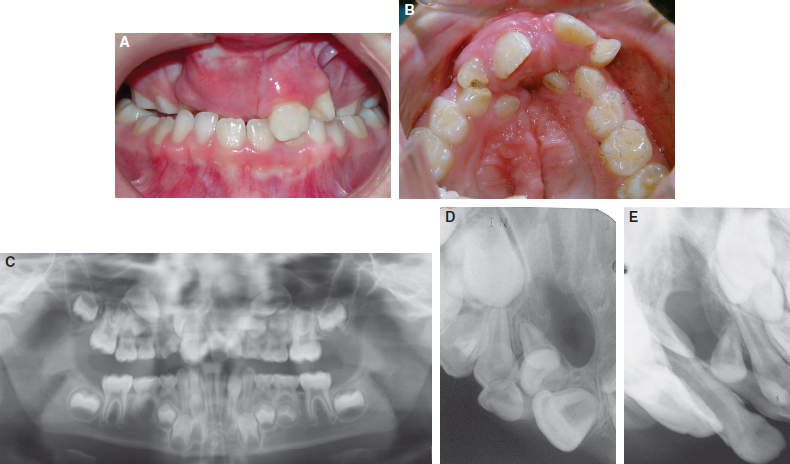

65 ○ The interdisciplinary team approach was developed to provide efficient and effective integrated care for the timing and management of infants born with orofacial clefts and craniofacial anomalies. ○ The orthodontist’s role has traditionally included considerations of both skeletal and dental growth and development. ○ Management of the postnatal growth of the nasomaxillary and mandibular components has been conveniently divided and integrated into four developmental stages: neonatal maxillary orthopedics, the primary dentition, the mixed dentition, and the adolescent and adult permanent dentition. ○ The timing and sequencing of alveolar bone grafts during the mixed dentition stage and orthognathic surgery during the permanent dentition stage require close collaboration of the orthodontist with the surgeon. ○ If skeletal malocclusion is severe in the primary or early mixed dentition, skeletal correction should be delayed until the permanent dentition stage, when a combined approach of comprehensive orthodontics and orthognathic surgery may lead to a more predictable correction. ○ The maxillary incisors adjacent to the cleft site may be tipped, rotated, malformed, or hypoplastic with an absence of bone in the cleft site to support the eruption of the permanent lateral and canine teeth. ○ Orthodontic alignment of maxillary incisors before secondary bone grafting must be limited by the available bone into which the teeth can be moved. ○ In patients with a missing maxillary lateral incisor at the cleft site, the edentulous space can be closed by prosthetic replacement of the lateral tooth (with a fixed partial denture or an endosseus implant) or by orthodontic mesialization of the canine tooth (canine substitution). The document “Parameters for Evaluation and Treatment of Patients with Cleft Lip/Palate or Other Craniofacial Anomalies,” developed by the ACPA in 19921 and later revised in 2009,2 has provided clinicians and third-party payers with guidelines to the scope, timing, and sequencing of treatment for patients with cleft lip or palate. Within the document, the role of the orthodontist is well defined, noting that this role should be a collaborative effort with other dental, medical, and allied health professionals. Emphasis is given to the monitoring of craniofacial growth and development and to providing treatment when necessary to achieve optimal function and appearance. Delivery of orthodontic treatment is recommended in discrete stages of the skeletodental development of the craniofacial complex to prevent continuous treatment from the early mixed dentition to the permanent dentition. These concepts are further explained in texts outlining the role of the orthodontist in the management of cleft lip and palate.3,4 The purpose of this chapter is to discuss the orthodontic principles that govern the contemporary management of patients with an orofacial cleft, from diagnostic considerations to issues of timing and sequencing of treatment. The team approach to the comprehensive care of children born with orofacial clefts requires collaboration among the orthodontist and the other members of the team (Fig. 65-1). The timing and sequencing of orthodontic care requires prioritizing each patient’s other health care needs in the context of an integrated treatment plan derived from a consensus of all team members. Orthodontic interventions may be conveniently divided into four distinct periods defined by age and dental development: neonatal period, primary dentition, mixed dentition, and permanent dentition. Neonatal (or infant) orthopedics occurs during the early postnatal period, usually in the first few months after birth, unless contraindicated by other medical conditions. This intervention was introduced in the 1960s by Burston5 and McNeil6 with the intention that early alignment of the maxillary segments would subsequently allow the dentition to erupt into a more normal occlusion and eliminate the need for orthodontic correction. As this intervention gained popularity, the complexity of the appliances used increased, with both intraoral and extraoral components. The least invasive technique was simple extraoral lip taping (Fig. 65-2). Fig. 65-2 An infant with a complete unilateral left cleft lip and palate. A, Defect before orthopedic intervention. B, Presurgical orthopedics with lip taping to approximate the segments. C, Postsurgical result of definitive lip repair NAM involves an intraoral molding plate, nasal stents, and extraoral taping.7,8 Intraorally, the alveolar ridges are molded to reduce the width of the cleft, achieving approximation of the segments to within 1 to 2 mm of each other. Extraorally, the simultaneous use of nasal stents and taping allows for lengthening of the columella and reshaping of the lower lateral alar cartilages in both bilateral and unilateral clefts. This orthopedic treatment prepares the infant for a one-stage primary lip-nose repair in combination with a gingivoperiosteoplasty to close the alveolar defect. The lengthening of the columella that is achieved from NAM may eliminate or reduce future surgical procedures for columellar lengthening. Because these clinical interventions are performed early in the neonatal period, longitudinal follow-up into adolescence is necessary to evaluate the long-term effects of these early interventions on subsequent nasomaxillary growth. Inspired by the Eurocleft retrospective intercenter project of the 1990s and with advances in clinical outcomes trial methodology, the Dutch intercenter prospective two-arm randomized clinical trial (RCT), also known as Dutchcleft, was designed to study the outcome of neonatal maxillary orthopedics in subjects with unilateral cleft lip and palate (UCLP).9,10 Infant orthopedics in this trial consisted of the use of passive intraoral plates that were adjusted every 3 weeks to guide the maxillary segments and that were replaced with new plates as primary teeth emerged. In a 2005 study by Prahl et al,11 no significant difference could be found between the two randomized groups of infants up to 2 years of age with respect to feeding, nutritional status, or somatic growth. When assessing speech development at age 2.5 years, Konst et al12 found a significant improvement in children treated with infant orthopedics compared with children who did not receive infant orthopedics, with acceptable cost-effectiveness of the orthopedic treatment in regards to speech development. Further reports from the RCT indicated that infant orthopedics had no significant effect on various measures of maxillary arch dimension at ages 4 and 6 years when compared with similarly aged children who had not been treated with infant orthopedics.13 Similar findings were reported with respect to dental arch relationships at ages 4 and 6 years, including overjet, overbite, and sagittal occlusion.14 Cephalometric analyses of soft tissue, skeletal, and dental structures revealed only minor differences at age 6 years between the group treated with infant orthopedics and the untreated group.15 Facial appearance was also evaluated longitudinally in the two groups. Any group differences in facial appearance observed at age 4 years were no longer observed at age 6 years, at which time the better ratings in the infant orthopedic group could only be detected by professional raters.16 The Dutchcleft trial continues to monitor the patients longitudinally into their adolescence. In their conclusions, the investigators warned that clinicians who promote different methods of infant orthopedics, including NAM, should evaluate the long-term effects of their interventions using the rigorous methodology of an RCT.15 In their systematic review of the long-term effects of presurgical infant orthopedics, Uzel and Alparslan17 analyzed eight RCTs and four controlled clinical trials (CCTs), with follow-up periods of up to 6 years. Their results indicate that infant orthopedics has no positive effect on the treatment outcomes evaluated until the age of 6 years, including maternal satisfaction, feeding, speech, facial growth, maxillary arch dimension, occlusion, and nasolabial appearance. If neonatal orthopedics is recommended and feasible, it should be completed in the first few months of life so that definitive surgical lip repair can be achieved within the first 6 months. Palate repair is usually delayed until later in the first year of life. An ongoing controversy relates to the balance between the advantages of restoring the anatomy of the palate in the prelinguistic period and the effects of surgical scar tissue constraining the growth and development of the nasomaxillary complex. Ross18 evaluated the outcomes of both active and passive appliances in children with UCLP at age 10 years after neonatal presurgical infant orthopedics. The results in these groups were compared with those of untreated subjects at matched ages. This cephalometric study of facial growth in treated and untreated children with UCLP reported no beneficial long-term effect of neonatal orthopedics, although some negative effects were observed in those children who had received extraoral taping. As part of the Americleft intercenter study, Daskalogiannakis et al19 found that children with UCLP who were cared for at the only treatment center among the four participating North American treatment centers that did not employ any kind of infant presurgical orthopedics as part of their primary management protocol had the largest mean maxillary prominence (SNA angle) and maxillomandibular convexity (ANB angle) during the mixed dentition stage. None of the centers that provided infant orthopedics used NAM as their presurgical approach, but rather relied on extraoral taping with or without intraoral plates. Clearly, case-controlled studies are needed to establish the long-term effect of infant presurgical orthopedics on various outcomes including growth, dentoskeletal relationships, aesthetics, and socioemotional measures, among others. The primary dentition has usually fully erupted by the time the child is 2.5 to 3 years of age. At this age, the facial soft tissues may mask an underlying skeletal deficiency (Figs. 65-3 and Figs. 65-4). As the toddler grows into a young child, growth of the nasomaxillary complex lags behind that of the mandible, resulting in increasing midfacial deficiency. This may be reflected in the dentition as anterior or posterior crossbites. Patients with bilateral cleft lip and palate (BCLP) may have severe constriction of the posterior segments and protrusion or extrusion of the premaxillary segment (Fig. 65-5). The unilateral or bilateral crossbite may be associated with a functional mandibular shift, which is an early indicator for orthodontic treatment in the primary dentition. However, because the crossbite is likely to recur with the eruption of the permanent successors, a decision may be made to postpone orthodontic intervention until the mixed dentition. Fig. 65-3 A, A 6-year-old girl with repaired complete bilateral cleft lip and palate. B, Her mildly prominent maxilla. C, The primary dentition. D, The bilateral crossbite. E, A palatal fistula and primary laterals that erupted ectopically behind the premaxilla. Fig. 65-4 A, A 7-year-old boy with repaired complete unilateral left cleft lip and palate. B, His mild bimaxillary retrusion. C, The early mixed dentition period. Fig. 65-5 A 5-year-old boy with repaired complete bilateral cleft lip and palate. A, The severe extrusion of his premaxillary segment. B, The premaxillary segment out of the vertical plane of occlusion. C, The severe constriction of the posterior segments and extrusion of the premaxillary segment. Labial and palatal oronasal fistulas are present. Constriction of the dental arch is manifested in both the transverse and sagittal dimensions of the maxilla. Early skeletal midfacial deficiency has been addressed with some success if treated in the primary or early mixed dentition by a protraction face mask (Fig. 65-6). More recently, several studies have reported on the use of miniscrews, or temporary anchorage devices, to support the mandibular dentition while intermaxillary elastics are used to orthopedically protract the maxilla.20,21 Although the occlusal correction includes dentoalveolar proclination of the incisors, the modification and redirection of the skeletal mid-facial deficiency may be transitory. Continued growth restriction of the nasomaxillary complex results in failure to keep pace with normal mandibular growth. Consequently, malocclusion is often reestablished during the late mixed dentition and into the adolescent permanent dentition. Long-term follow up reveals biologic variability in response to the protraction facemask.22 The most logical time for the intervention is when the patient is younger than 10 years of age, during which time the circummaxillary sutures are more responsive. However, a severe malocclusion in the primary or early mixed dentition is unlikely to be corrected with growth modification, which may be a costly and unnecessary burden to the patient and result in questionable and often transient benefit. In such severe malocclusions, skeletal correction should be delayed until the permanent dentition stage, at which time comprehensive orthodontics in combination with orthognathic surgery or maxillary distraction may be more predictably reliable options. Fig. 65-6 An 8-year-old boy with repaired complete unilateral right cleft lip and palate with sagittal and transverse maxillary deficiency. A, The lateral radiograph showed 7 mm reverse overjet. B, Protraction facemask with elastics attached to palatal hooks on expander. C, Palatal expander with bands cemented on the maxillary second primary molars and canines, with palatal hooks to attach elastics. D, Lateral and anterior crossbites improved with palatal expansion and maxillary and dental protraction. E, Facial profile after 9 months of protraction facemask therapy and palatal expansion. F, Correction of anterior and posterior crossbite; the maxillary retainer is in place. G, Superimposition of initial and postprotraction lateral cephalogram tracings shows correction of reverse overjet by incisor proclination and mild maxillary advancement. (Black lines, initial profile at age 8 years; red lines, after 9 months of protraction facemask therapy.) Transition in the child’s dental development occurs between 6 and 12 years of age, as the primary dentition exfoliates and the permanent teeth erupt. Midfacial deficiency at this phase makes the mandible appear prognathic, thus resulting in a concave facial profile (Fig. 65-7). Eruption of the permanent teeth coincides with a period of psychosocial transition during preadolescence when the degree of friendship intimacy intensifies and independence from parents increases.23 Ward et al24 reported that the presence of an orofacial cleft decreases the oral health–related quality of life (OHRQoL) in children and adolescents. In preadolescents with craniofacial anomalies, dissatisfaction with appearance is related to social withdrawal, social anxiety, and self-consciousness.25 This is also the period during which the greatest advances have been made in restoring the bone in the cleft site through the use of secondary alveolar bone grafts, which improve the periodontal support of teeth adjacent to the cleft site and thus reduce or eliminate the need for extraction and prosthetic replacement of compromised teeth. The orofacial cleft disrupts the dental lamina in the cleft site so that the developing permanent teeth may be missing, malformed, or supernumerary. The incisors adjacent to the cleft site may be misplaced, rotated, malformed, or hypoplastic with an absence of necessary bone in the cleft site to support eruption of the permanent lateral incisor and canine (Fig. 65-8). Alveolar bone grafting restores the continuity of the alveolar ridge and allows for closure of oronasal fistulas. Transverse maxillary constriction may be the consequence of scar tissue formation after surgical repair of the secondary palate, resulting in a characteristic omega- or V-shaped arch form, reflected in anterior and posterior dental crossbites (Fig. 65-9). A maxillary expansion appliance is often recommended when the first permanent molars and incisors erupt. Collaboration between the surgeon and the orthodontist in the mixed dentition stage to coordinate the treatment sequence assists in achieving a successful alveolar bone graft with healthy adjacent teeth. Fig. 65-7 A, Same patient as in Fig. 65-4 at 9 years of age. B, The patient had a mild midface deficiency. C, An anterior crossbite was evident during this mixed dentition period. Fig. 65-9 A, The same patient as in Figs. 65-4 and 65-7, shown at age 9 years, with bilateral posterior and anterior crossbites. Note the severely rotated maxillary central incisor next to the cleft. B, The V-shaped arch form and palatal scarring. Primary alveolar bone grafting typically involves the placement of a bone graft in the neonatal cleft site at the time of primary surgical lip repair and hence before eruption of the primary incisors. Data suggests that this method may be deleterious to maxillary growth, so most cleft palate teams prefer to defer bone grafting until further maxillary growth and development has occurred.26 Secondary, or delayed, alveolar bone grafting is performed after primary lip repair and is classified according to the age at which the bone graft is placed: early secondary bone grafting (2 to 5 years), intermediate secondary bone grafting (6 to 15 years), or late secondary bone grafting (adolescence to adulthood). The principles of secondary bone grafting were first introduced by Boyne and Sands.27,28 In 1986, Bergland et al29 studied 378 consecutive patients who had undergone secondary alveolar bone grafting, showing that the best outcomes were achieved in patients in whom the bone graft was performed before the eruption of the maxillary canine. This report was followed by a cephalometric study that compared maxillary growth in children who received secondary alveolar bone grafting between the ages of 8 and 12 years with the maxillary growth in children who did not have a bone graft.30 There was no adverse effect of bone grafting on anteroposterior or vertical maxillary growth, a finding attributed to the postponement of grafting until most of the growth of the anterior maxilla had occurred and to the ability of the grafted bone to develop vertically with the alveolus.30 Since the publication of these landmark articles, current opinion supports the intermediate period as the most appropriate time for grafting. This practice has the greatest benefits and least risk for interfering with midfacial and skeletodental growth and development. Levitt et al31 demonstrated that there were no significant differences in maxillary sagittal or vertical growth after secondary bone grafting in patients with complete UCLP when compared with that in patients with similar clefts who did not receive a bone graft. The multicenter Eurocleft study of treatment outcomes in patients with complete cleft lip and palate compared craniofacial form in individuals treated at five European centers.32 The only center performing primary bone grafting obtained less favorable results in vertical maxillary growth, soft tissue sagittal relationships, and soft tissue facial proportions than the centers that performed secondary bone grafting between the ages of 8 and 11 years. Moreover, the center that used primary bone grafting obtained the least favorable dental arch relationships, with almost 50% of the patients needing surgical correction of maxillary retrusion at 17 years of age.33 In Americleft, the North American intercenter study of treatment outcomes in patients with complete UCLP, the only center performing primary bone grafting obtained the least favorable dental arch relationships, lowest maxillary prominence, and least favorable maxillomandibular relationships.19,34 Further justification for performing alveolar bone graft surgery during the mixed dentition period is that patients at this age are usually cooperative with the orthodontic procedures, such as maxillary expansion, that may be indicated before grafting.35 The donor site for graft harvest, typically the anterior iliac crest, has an acceptable volume of bone for successful grafting at this age.35 A survey of alveolar bone grafting practices among ACPA teams across North America revealed a consensus for the type of alveolar bone grafting performed: most of the centers perform intermediate secondary alveolar bone grafting.26 Therefore the following discussion focuses on alveolar bone grafting during this time period. A bone graft placed before eruption of the teeth adjacent to the cleft (especially the lateral incisor or canine when located on the posterior segment) provides a bony matrix to enable the eruption of these teeth into a continuous alveolar ridge, generating additional alveolar bone in the area29 (Fig. 65-10). Generally, grafting is done before the eruption of the permanent maxillary canine on the cleft side, which is usually located in the alveolar segment posterior to the cleft. Teeth directly adjacent to the cleft, particularly maxillary central or lateral incisors located on the proximal (mesial) segment, often erupt into unfavorable positions and may be ectopic, be rotated, or have an unfavorable axial inclination. This malposition is usually a reflection of the anatomy of the alveolar cleft, which is usually narrower at the alveolar margin and wider at the piriform aperture, thus limiting the amount of bony support for the teeth, especially along the root surface directly facing the cleft. Radiographs of these teeth often demonstrate a thin layer of cortical bone along their distal surface (see Fig. 65-10), bone that may be at risk for resorption if nonjudicious presurgical orthodontic uprighting is carried out. If a bone graft is placed before extensive orthodontic alignment of erupted teeth adjacent to the cleft, crestal bone heights are preserved, and postsurgical orthodontic alignment can be accomplished with minimal risk of bone resorption while ensuring adequate bony coverage of the roots. Oronasal fistulas can allow for nasal air escape with speech and may contribute to velopharyngeal dysfunction in patients with cleft lip and palate.36 A three-layered closure technique, with the graft interposed between the two soft tissue layers, yields a high success rate of fistula closure. Surgical closure of oronasal fistulas with secondary alveolar bone grafting often results in a significant improvement in speech, manifested as decreased nasality and nasal emission.37 Occasionally, large palatal fistulas cannot be closed at the time of alveolar bone grafting without compromising the integrity of the graft. On a case-by-case basis, surgeons may elect to close the palatal fistula in a separate surgical procedure, usually before alveolar bone grafting. Fig. 65-10 A, A bone defect at the cleft site in a 10-year-old patient before alveolar bone grafting. More than two thirds of the roots of the transposed lateral incisor and canine have developed (close to eruption). Note the thin layer of bone covering the adjacent central incisor. No orthodontic incisor alignment is planned. B, Periapical radiograph taken 4 months after alveolar bone grafting, showing excellent fill of the cleft defect with cancellous bone. The canine is erupting through the grafted bone. Alveolar bone grafting contributes to improved nasal and lip symmetry and provides a stable platform on which the nasal structures are supported.38 If performed alone or in combination with tip rhinoplasty (often as a separate procedure) alveolar bone grafting often yields aesthetic benefits. After a successful bone graft, the orthodontist can move the teeth bodily and upright roots into the cleft site without risk of compromising their periodontal support.29,39 The prosthodontist also can achieve a more aesthetic and hygienic prosthesis to replace missing teeth in the cleft area.39 Insertion of endosseous implants into the grafted cleft is possible and provides functional stimulation to the transplanted bone.40 Patients with bilateral clefts present with varying degrees of mobility of the premaxilla, which usually remains unstable throughout life.29 In such cases, secondary alveolar bone grafting stabilizes the premaxilla, allowing patients to have functional incisors with adequate stability to serve as abutments for fixed prostheses.29,39 The optimal time for performing secondary alveolar bone grafting can be established according to the age of the patient or, alternatively, according to dental development as defined by stage of root development. Chronologic Age By definition, secondary bone grafting is done during the mixed dentition stage, before the eruption of the maxillary canine (or lateral incisor, if located in the alveolar segment posterior to the cleft). Once teeth have erupted into the cleft site, their limited periodontal support will not improve with a graft, because the transplanted bone will not adhere to the tooth surface.35 The height of the crest of alveolar bone eventually resorbs to its original level. It is therefore essential to perform the graft before the eruption of the permanent teeth adjacent to the cleft. This period may encompass a range of several years, from age 6 to 15 years, when grafting has a high success rate. However, evidence shows that the older the patient is at the time of surgery, the poorer the outcomes of secondary bone grafting.41 Therefore the available evidence supports an optimum age at which patients should receive bone grafts. Using chronologic age alone for defining the optimal age for grafting may not be clinically valid, because patients with cleft lip or palate have delayed development of the teeth compared with individuals without clefts.42 Moreover, teeth adjacent to the cleft side demonstrate more developmental delay than the contralateral teeth.42 Dental development, based on assessment of the number of permanent teeth erupted and the extent of root formation, represents a more accurate indicator of the optimal timing for the bone grafting procedure than does chronologic age alone. Maxillary Canine Development One developmental indicator that has been proposed for establishing the optimal timing for grafting is the root formation of the permanent maxillary canine on the cleft side. It has been recommended that the optimal timing for secondary grafting is when the maxillary canine has developed one half to two thirds of its final length, which generally occurs between the ages of 8 and 11 years39,43 (see Fig. 65-10). This is advocated because when the root has developed two thirds of its expected full length, accelerated eruption of the canine occurs, and it can then erupt spontaneously through the graft, bringing additional alveolar bone into the area. In a retrospective study of patients with non-syndromic UCLP, Mercado et al44 demonstrated a significant positive correlation between stage of canine root development at the time of surgery and the outcome of bone grafting. Maxillary Lateral Incisor Development A study of patients with UCLP demonstrated that the cleft-side permanent lateral incisor was present in 50.2% of patients.45 Of these patients, 76.5% had the permanent lateral incisor located on the posterior segment, distal to the cleft. When the maxillary lateral incisor is located in the posterior segment, alveolar bone adjacent to the cleft is generally insufficient to support the lateral incisor as it drifts anteriorly and occlusally along its eruptive path into the arch. In such cases, grafting before the eruption of the lateral incisor may be advisable to improve the prognosis of this tooth.46,47 The developmental indicator of one half to two thirds of canine root formation for timing of an alveolar bone graft may be too late when the aim is to preserve an existing lateral incisor. Lilja et al48 discourage the use of root formation as an indicator for graft placement, proposing the assessment of the thickness of bone covering the crown (of the lateral incisor or canine) to determine timing of bone grafting. They advocate that bone grafting be performed when there is a thin layer of bone covering the tooth distal to the cleft. Other studies have reported no significant relationship between the degree of radiographic canine eruption through the alveolar cleft and the outcome of secondary bone grafting.49,50 The sequencing of procedures associated with placement of an alveolar bone graft requires interdisciplinary communication and cooperation for a successful outcome. Orthodontists, general or pediatric dentists, oral surgeons, and plastic surgeons intervene in a coordinated fashion to ensure that one discipline’s efforts do not interfere, delay, or jeopardize those of the other disciplines. Parents and caregivers may be concerned about teeth (often supernumerary) that have erupted near the cleft, either palatally or high in the labial vestibule. Ectopic teeth present a challenge for the parents and patient to maintain good hygiene because of their location and limited accessibility. The role of the general or pediatric dentist is to ensure that the patient and parents are aware of the ectopic teeth and that they are instructed on good oral hygiene practices to maintain the teeth free of decay, out of traumatic occlusion, and not contributing to traumatic ulcerations of the surrounding mucosa. The preservation of these teeth before surgery maintains the supporting alveolus. The general or pediatric dentist should restore any decayed teeth adjacent to the cleft before the grafting procedure. On the other hand, erupted teeth adjacent to the cleft that have poor periodontal or restorative prognosis should be extracted at least 2 months before surgery to allow the soft tissues to heal (see Fig. 65-8). This will allow healthy mucosal flaps to be reflected, positioned, and sutured over the grafted bone at the time of surgery. Healthy ectopic primary or supernumerary teeth that have erupted along the line of the cleft should also be removed at least 2 months before surgery to allow access to the surgical site. Orthodontic treatment may be required presurgically to reposition maxillary teeth that are in traumatic occlusion or to expand a severely constricted maxilla, thus providing the surgeon better access to the cleft defect. In bilateral cases, a mobile premaxilla with anterior traumatic occlusion may need to be addressed with a posterior bite plane to minimize mobility, which may compromise the success of the grafts during the healing period.35 A severely extruded premaxilla may need to be intruded to level it with the posterior segments (Fig. 65-11). This can be done with an active intrusion arch ligated over a passive segmental wire to the maxillary incisors. Alternatively, miniscrews placed directly on the premaxilla may serve as a point of attachment during intrusion, repositioning, and stabilization of the premaxilla.20 Other surgical procedures such as minor aesthetic revisions of the nose and lip, as well as the insertion of tympanostomy tubes, may be undertaken during the same general anesthesia setting of the alveolar bone graft. Dental prophylaxis and restorative work are generally not performed in conjunction with the bone grafting procedure to minimize the release of bacteria and debris into the surgical site. Unerupted teeth with poor prognosis adjacent to the cleft can be removed by the surgeon intraoperatively once the mucosal flaps have been reflected.